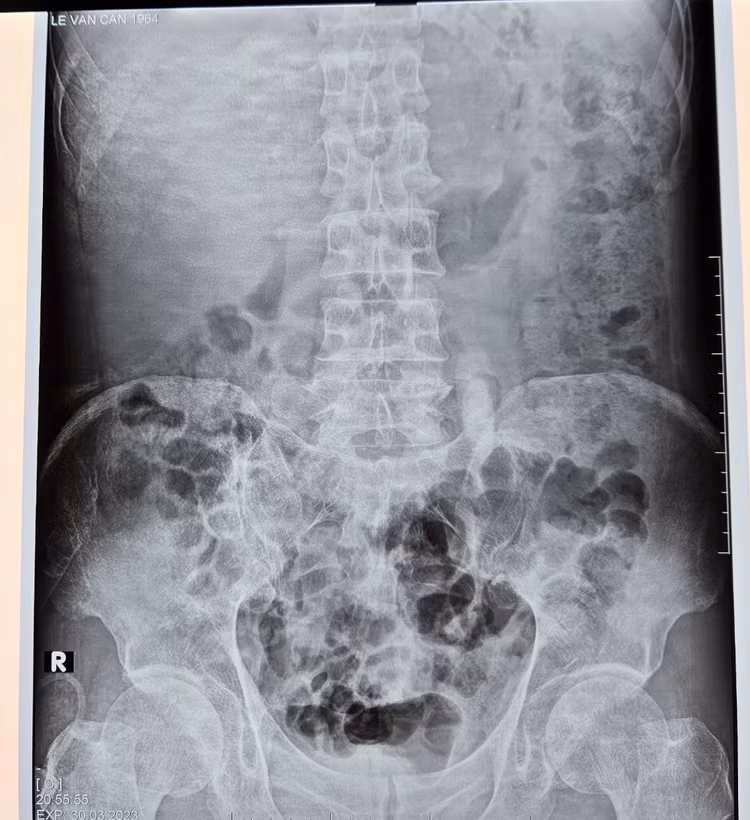

Tại thời điểm nhập viện, bệnh nhân ý thức lơ mơ, vã mồ hôi lạnh. Qua thăm khám, bác sỹ trực cấp cứu nhận định thấy bệnh nhân da niêm mạc nhợt, kèm theo tình trạng trụy tim mạch, không liên quan tới các yếu tố chấn thương. Kết hợp với các kết quả cận lâm sàng bệnh nhân được chẩn đoán: Sốc nhiễm khuẩn đường vào do vỡ ổ mủ từ thận vào khoang màng phổi trái, sỏi niệu quản trái 1/3 trên.

| Sỏi niệu quản trên phim chụp |